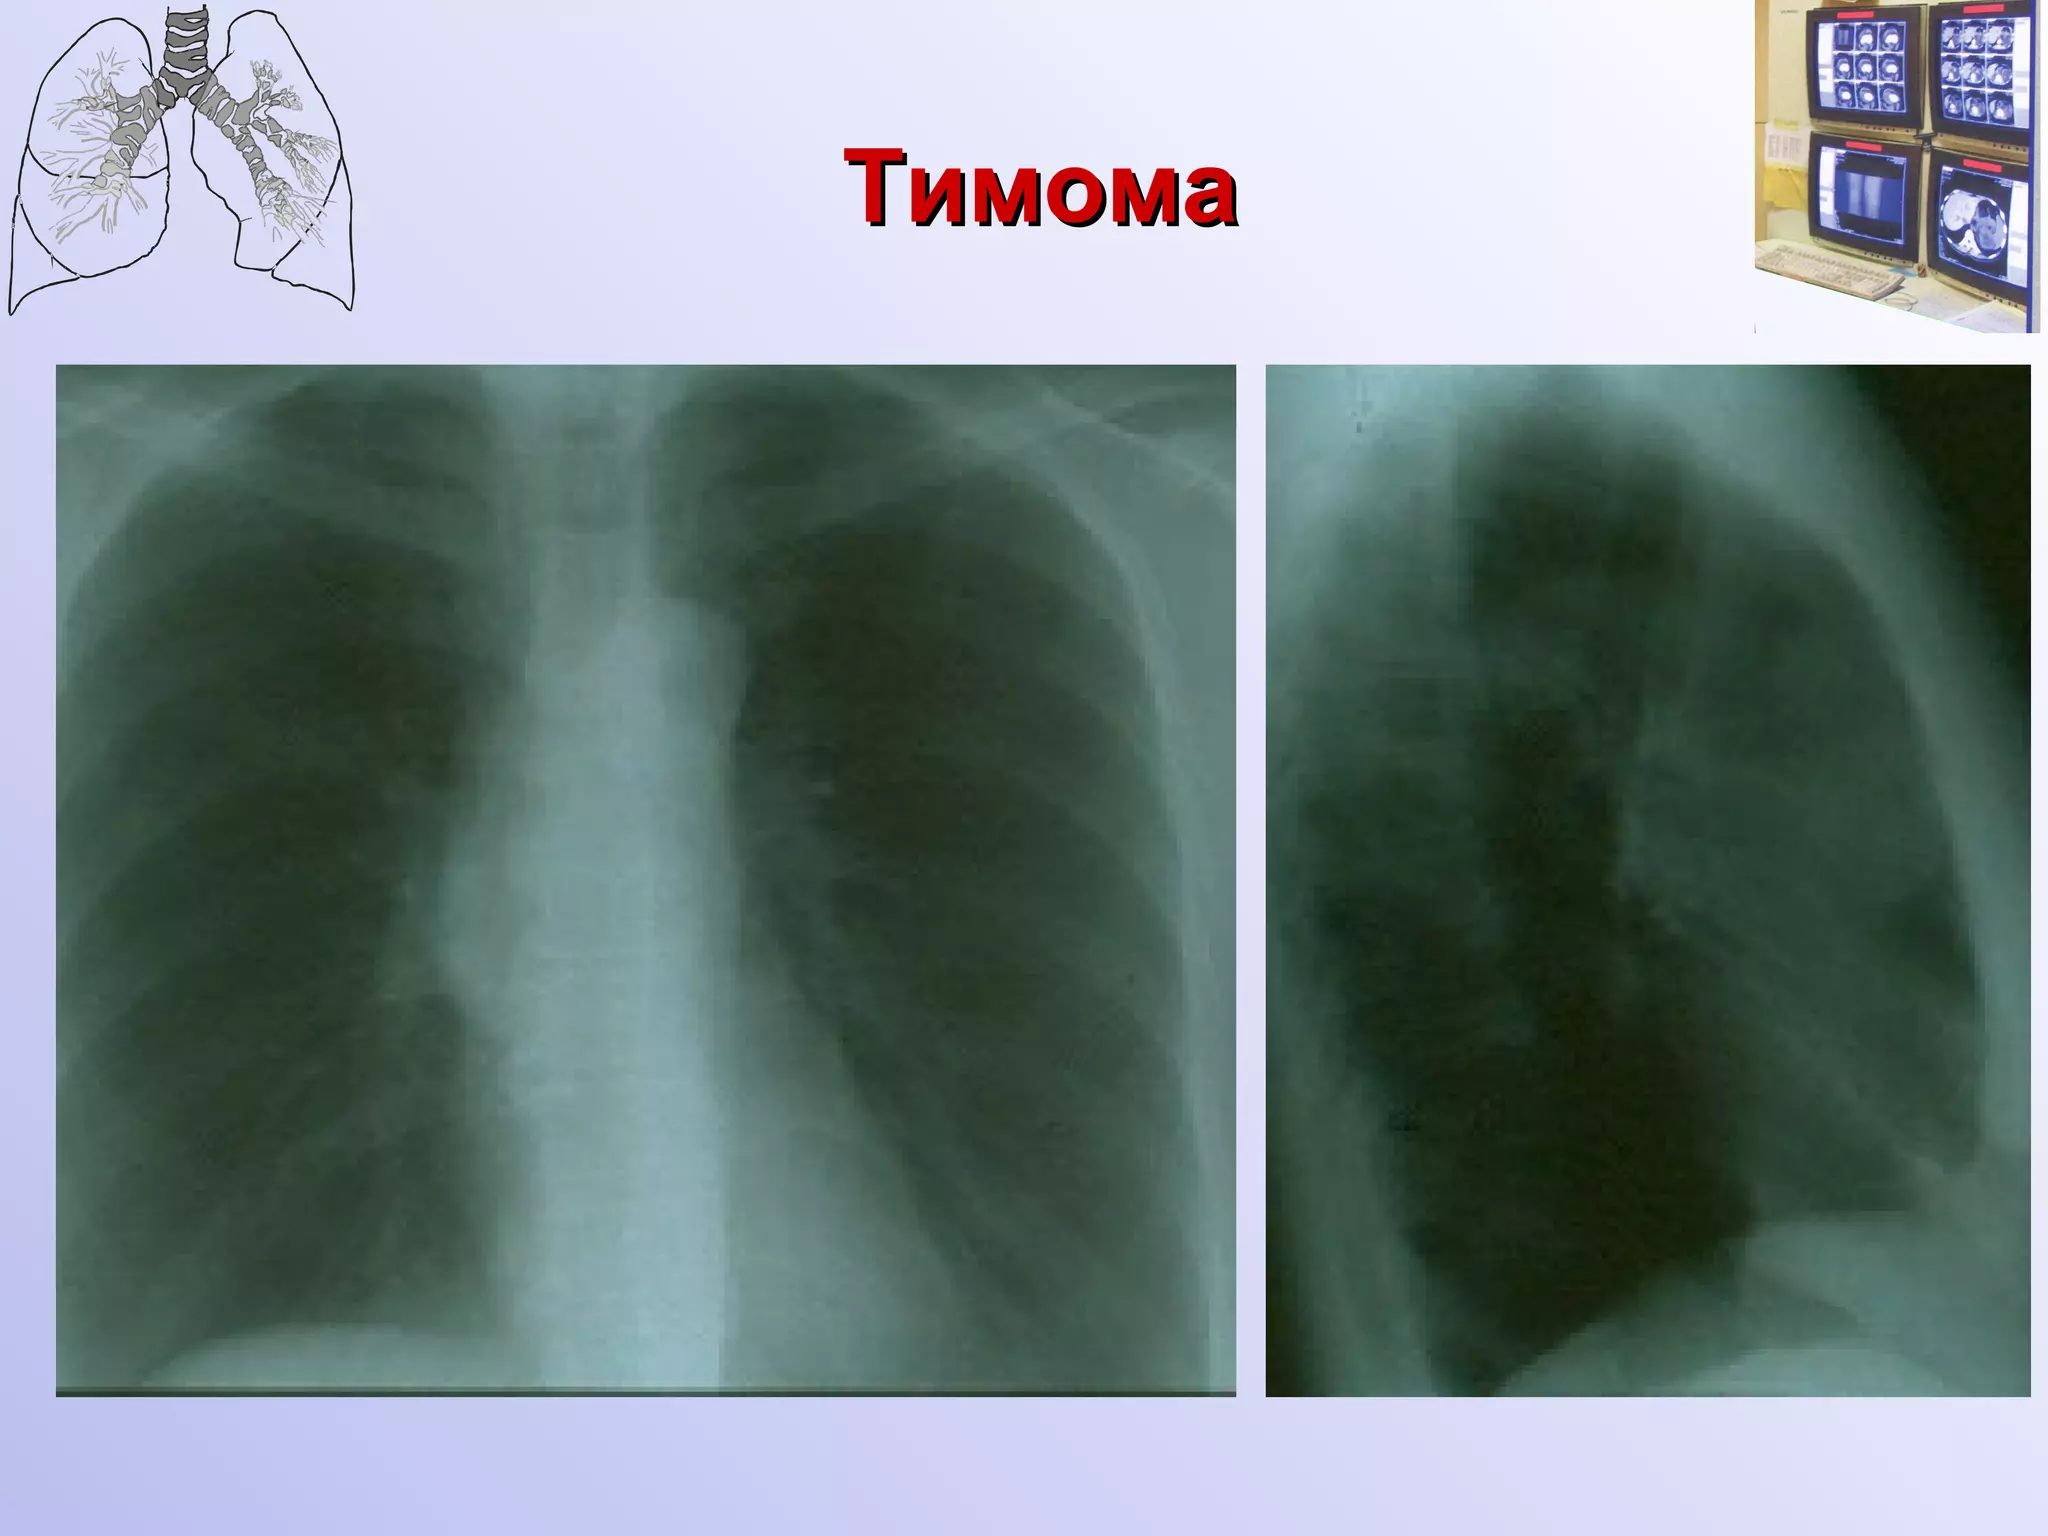

Рентгенологическая и КТ семиотика доброкачественных тимом Локализуется асимметрично в среднем этаже переднего средостения  При глотании не смещается Форма овоидная, неправильно шаровидная, грушевидная  Сплющена в передне-заднем размере, прижата к грудине Поверхность бугристая, контуры четкие Структура однородная, известковые включения встречаются крайне редко Отграничена капсулой

Тимома

Рентгенологическая и КТсемиотика доброкачественных тимом Локализуется асимметрично в среднем этаже переднего средостения При глотании не смещается Форма овоидная, неправильно шаровидная, грушевидная Сплющена в передне-заднем размере, прижата к грудине Поверхность бугристая, контуры четкие Структура однородная, известковые включения встречаются крайне редко Отграничена капсулой

• 11.

• 12.